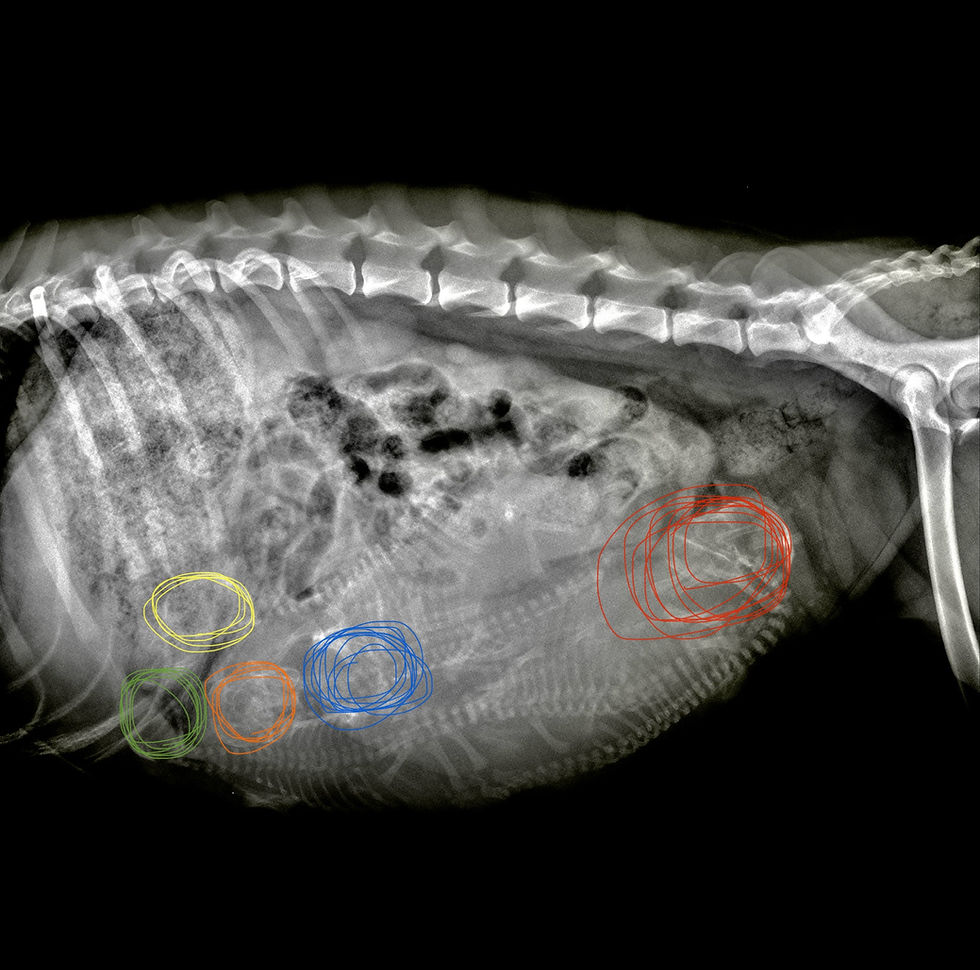

After a nervous wait, we finally got confirmation by Xray, that we were to be expecting 5 puppies!